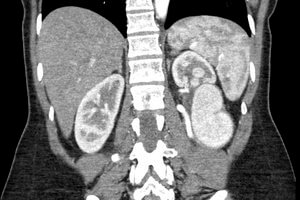

34 year old post-partum female who presented to her gynecologist with left-sided flank pain.

Comment: This post-partum patient developed a very large left renal artery aneurysm that was at significant risk for rupture. Given the size of the aneurysm and the branch of the renal artery supplying the aneurysm, we proceeded with embolization of the feeding vessel with an Amplatzer Vascular Plug. This has ultimately led to thrombosis of the aneurysm, as evidenced on subsequent follow-up imaging with ultrasound.